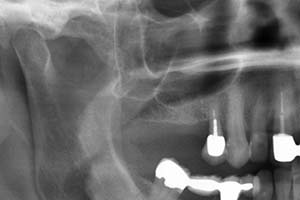

Ein weiterer oralchirurgischer Eingriff ist der sogenannte Knochenaufbau. Es bestehen viele Gründe wodurch ein Knochenaufbau, die sogenannte Knochenaugmentation, erforderlich werden kann. Eine fortgeschrittene Parodontitis kann zu Knochenrückgang in verschiedensten Bereichen des Kiefers führen. Die Knochenathrophie kann zudem auch durch Zysten im Kieferbereich erfolgen. Fehlende Zähne, die nicht durch Implantate ersetzt wurden, führen meist dazu, dass sich auch hier der Kieferknochen zurückbildet. Wenn herausnehmbare Prothesen schlecht und wackelig sitzen, kann der Vorgang des Kieferknochenabbaus noch verstärkt werden.

Knochenaufbauten oder sogenannte Kieferaugmentationen werden heutzutage sehr häufig durchgeführt. Von einfachen Maßnahmen nach einer Zahnextraktion zur Volumenstabilisierung bis hin zu komplexen Transplantationen körpereigenen Knochens führen wir bei uns in der Zahnärztlichen Praxisgemeinschaft Kampnagel verschiedenste Augmentationstechniken zum Kieferaufbau durch.

Bei einigen oralchirurgischen Operationen ist es in Sonderfällen möglich, dass kein eigenes Knochenmaterial verwendet werden kann, z.B. bei Sinusliftoperationen (Verbreiterung des Oberkiefers im Bereich der Kieferhöhle) oder bei einer Kieferkammverbreiterung. Hier versuchen wir stets als Alternative künstliches Knochenersatzmaterial zu verwenden um Ihnen ein zweites Operationsgebiet zu ersparen. Unter Umständen werden Membranen zur Fixierung des Augmentats benötigt.